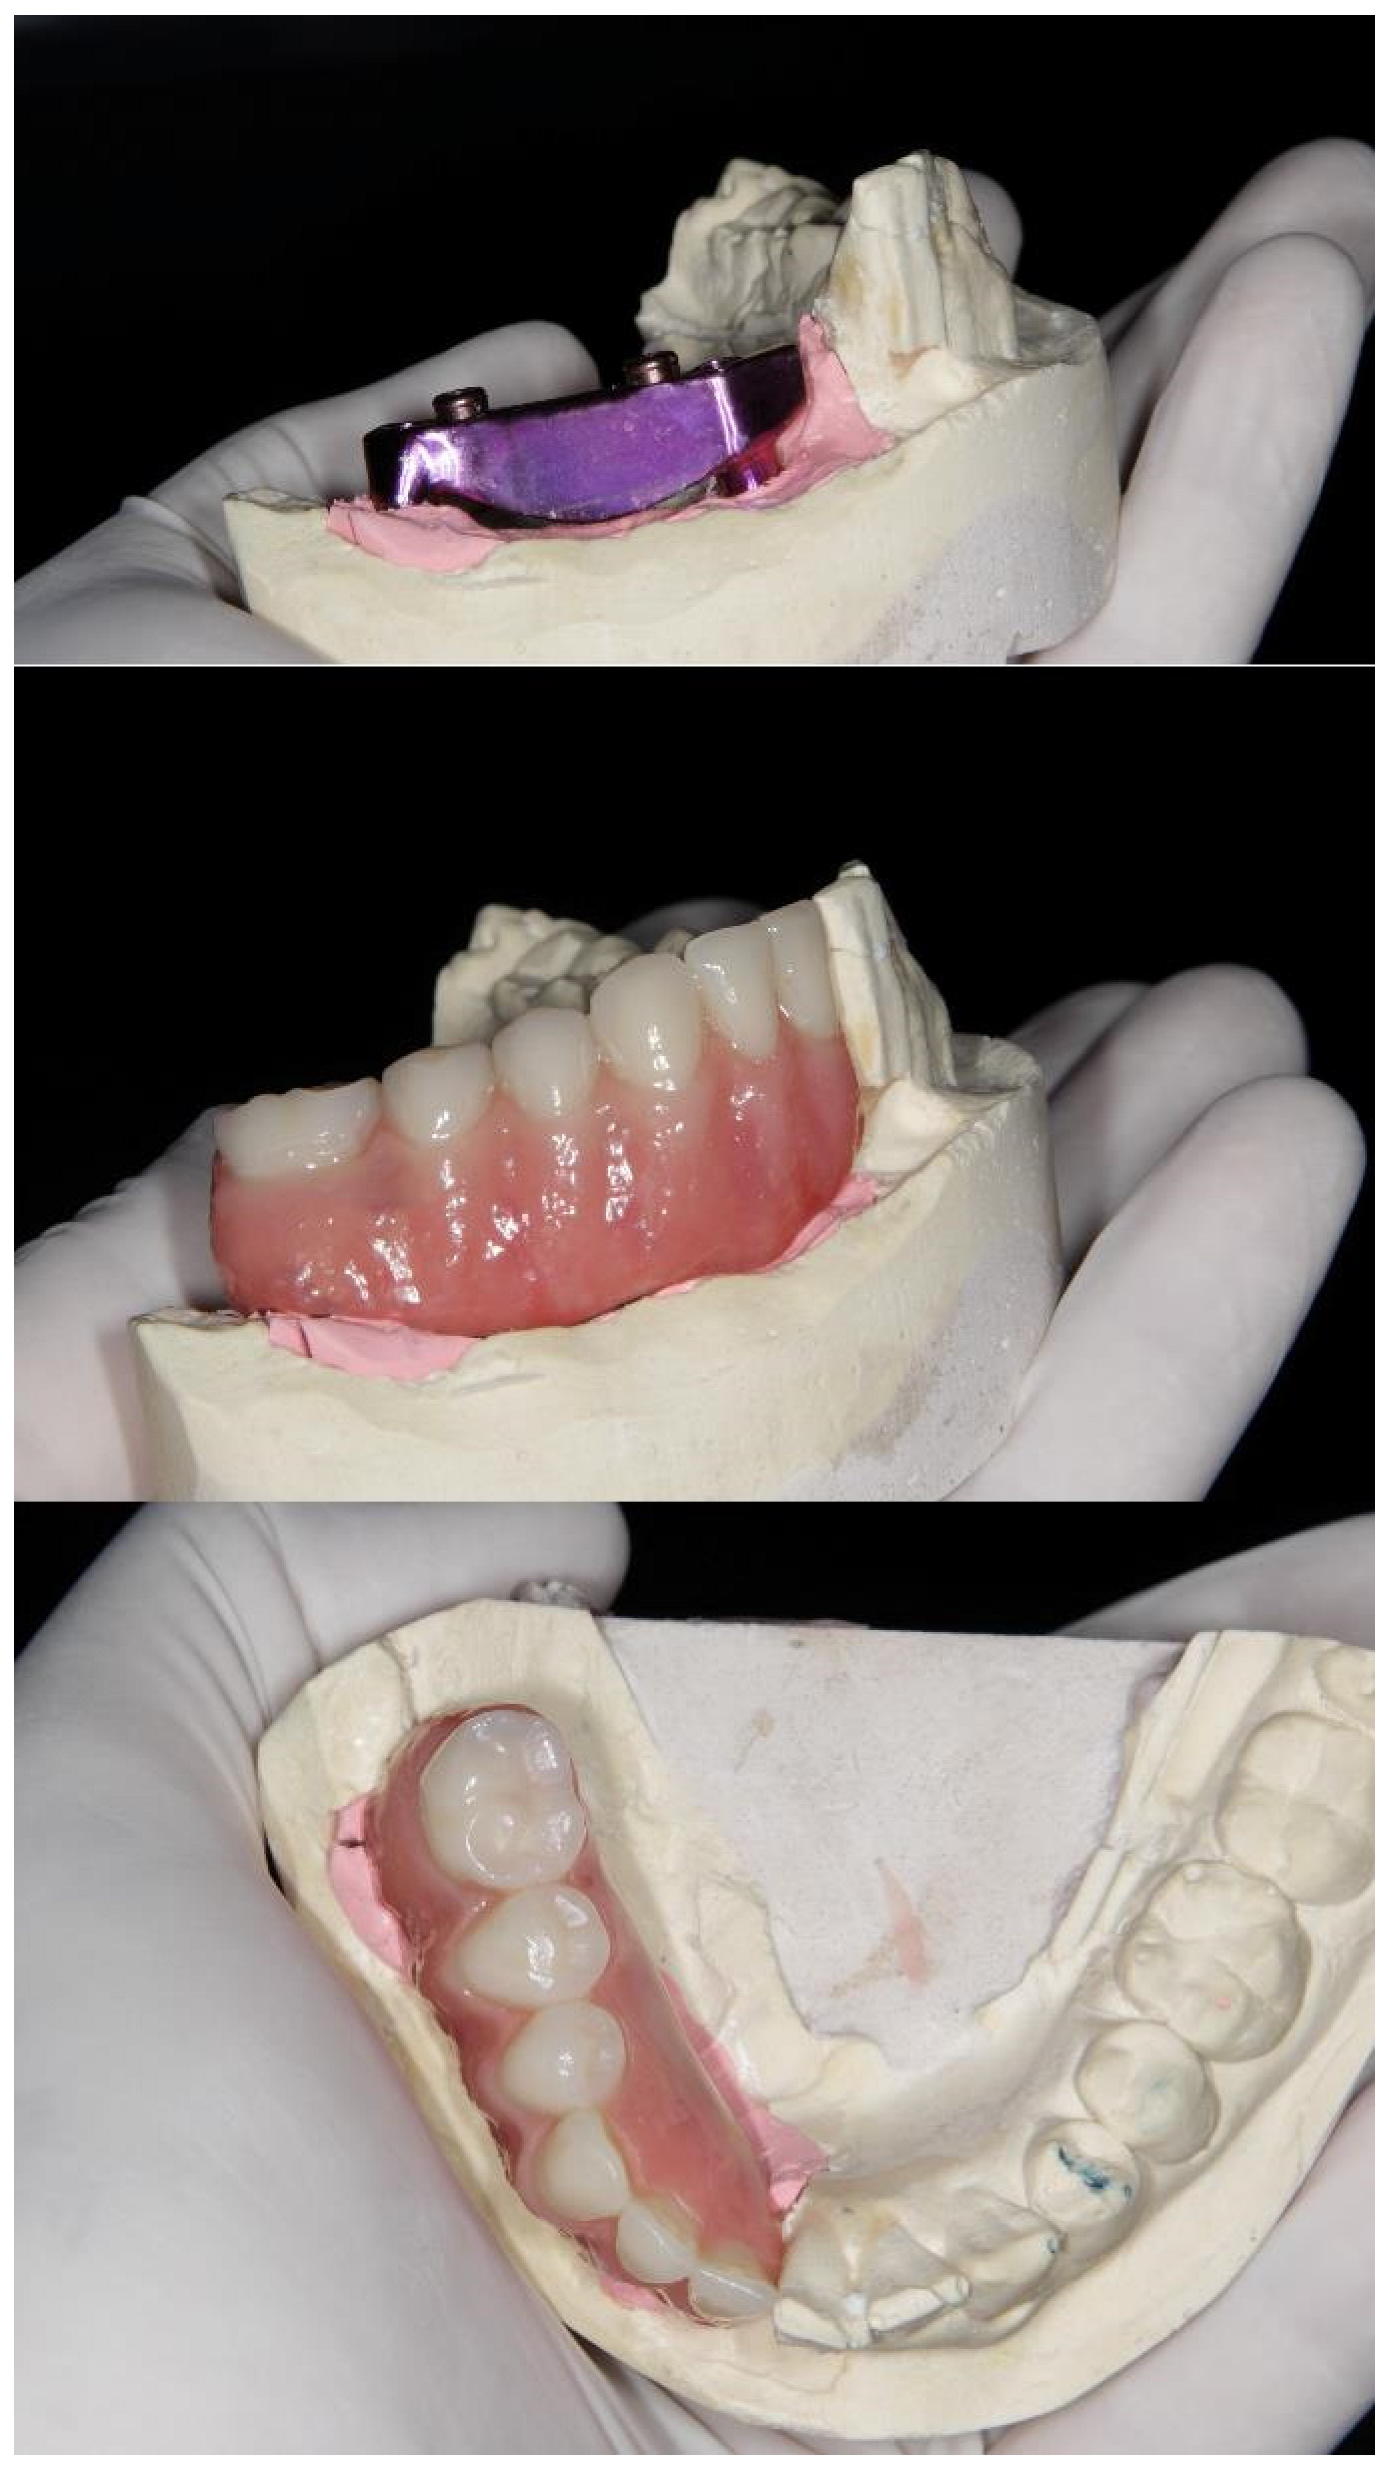

2. Materials and Methods

Clinical Case

| 2023 | Surgery of 4 implants in the jaw |

| 2023–2024 | Start with rehabilitation phase |

| 2024 | Prosthetic installation |